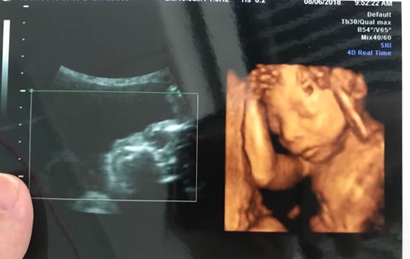

四维超声是一种比较先进的检查方式,也是实时的动态三维超声,一般来说通过四维超声来辨别宝宝性别是比较准确的,四维单子上出现了四个字的就是怀了男宝,更多关于生男生女的相关内容尽在试管婴儿网,欢迎关注。

这四个字就是肾盂分离,为什么说单子上有这四个字是怀了男宝呢,其实这和胎儿在母亲体内的行为有关,双侧肾盂分离提示是男宝的概率占到80%到90%,这也是因为男宝宝独特的生理性结构特征容易出现尿潴留的情况,也就是说男宝宝在妈妈体内是会憋尿的,从而导致肾盂被充盈而出现变大的现象,只要肾盂分离不超过10mm那就是正常的。

一:在彩超单上会印,顶头最右边有两行字,是英文字母和数字组成的,第一行是日期,第二行是时间,如果第一行是M开头,那就是male男,如果是F开头就是female女,第二行打头的T是时间的意思。

二:彩超单上通常有双侧肾盂分离,那90%是男孩;如果是双侧肾盂未见明显分离,那95%是女孩。

三:彩超单上很小英文字母Qual high 1是女孩,2是男孩。

四:通过四维彩超图看清胎儿性别,在六个月以后照四维彩超,只要宝宝的姿势是正面不是给个背影什么的,是男是女一看就知道。不过因为国家明文规定不能查胎儿性别,所以医生不会把能明显看出性别的一面照给妈妈看。